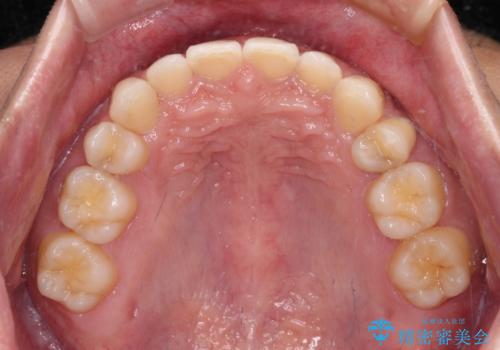

著しいディープバイトと隙間だらけの歯列

- 歯のデコボコと歯の隙間を気にして来院された患者様です。

隙間の原因は、埋伏や前後に重なってしまっている上顎小臼歯と、下の前歯が見えなくなるくらいのディープバイトで、それらを改善する必要がありました。

アンカースクリューを用いて下に位置している上顎前歯を持ち上げるとともに、ワイヤー装置によりディープバイトの原因である奥歯の傾斜を改善することで、矯正治療を行っていくこととしました。

顕著なディープバイトのため、頻繁に装置が脱離することがあり、治療期間が想定よりも長くかかることがありますが、当初の予定期間で無事に治療を終えることができました。